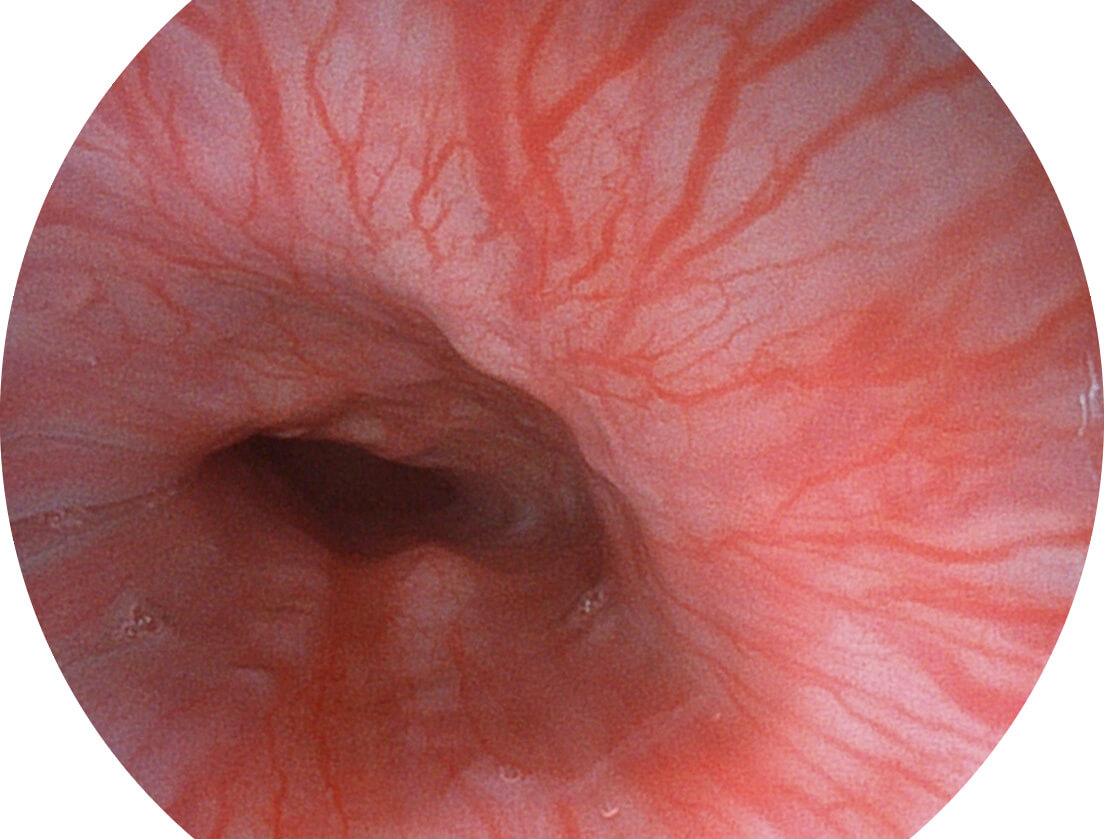

图像具有高亮度、高黏膜血管颜色对比度的特点,且不改变粘液、食物残渣、粪便的基本颜色,可在中远景下进行观察,助力消化道早期疾病的诊断。

白光图像